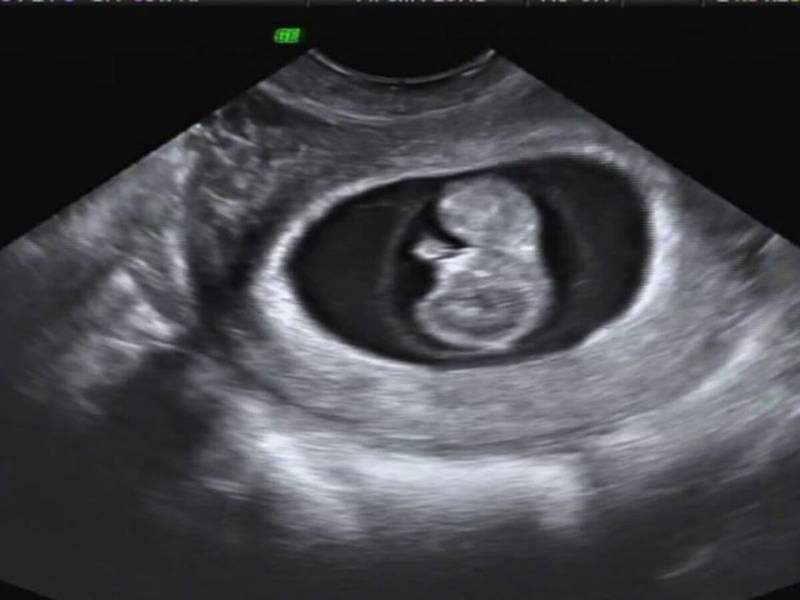

Chẩn đoán phù nhau thai thường dựa vào siêu âm thai, trong đó bác sĩ sử dụng sóng âm thanh tần số cao chụp ảnh bên trong cơ thể và nhận biết thai nhi có bị phù nhau thai hay không trong các buổi khám thai định kỳ. Ngoài ra, nếu bạn thấy thai nhi di chuyển ít thường xuyên hơn bình thường hoặc gặp phải các biến chứng khác như huyết áp cao trong thai kỳ, bạn cũng có thể được khám siêu âm để đánh giá lại tình trạng.

Để đảm bảo chẩn đoán chính xác và mức độ nghiêm trọng của bệnh, các xét nghiệm khác có thể được thực hiện, bao gồm xét nghiệm máu của thai nhi, chọc ối (amniocentesis), và siêu âm tim thai để kiểm tra các dị tật cấu trúc của tim.